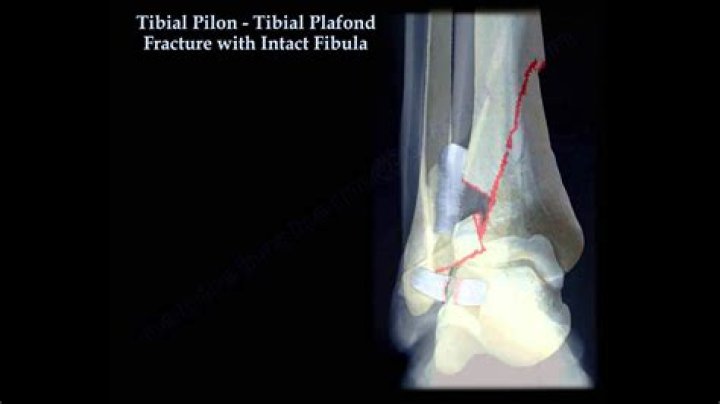

Where is the tibia plafond?

Tibial plafond fractures occur just above the ankle joint and involve that critical cartilage surface of the ankle. The other major factor that must be considered with these injuries is the soft-tissue around the ankle region.